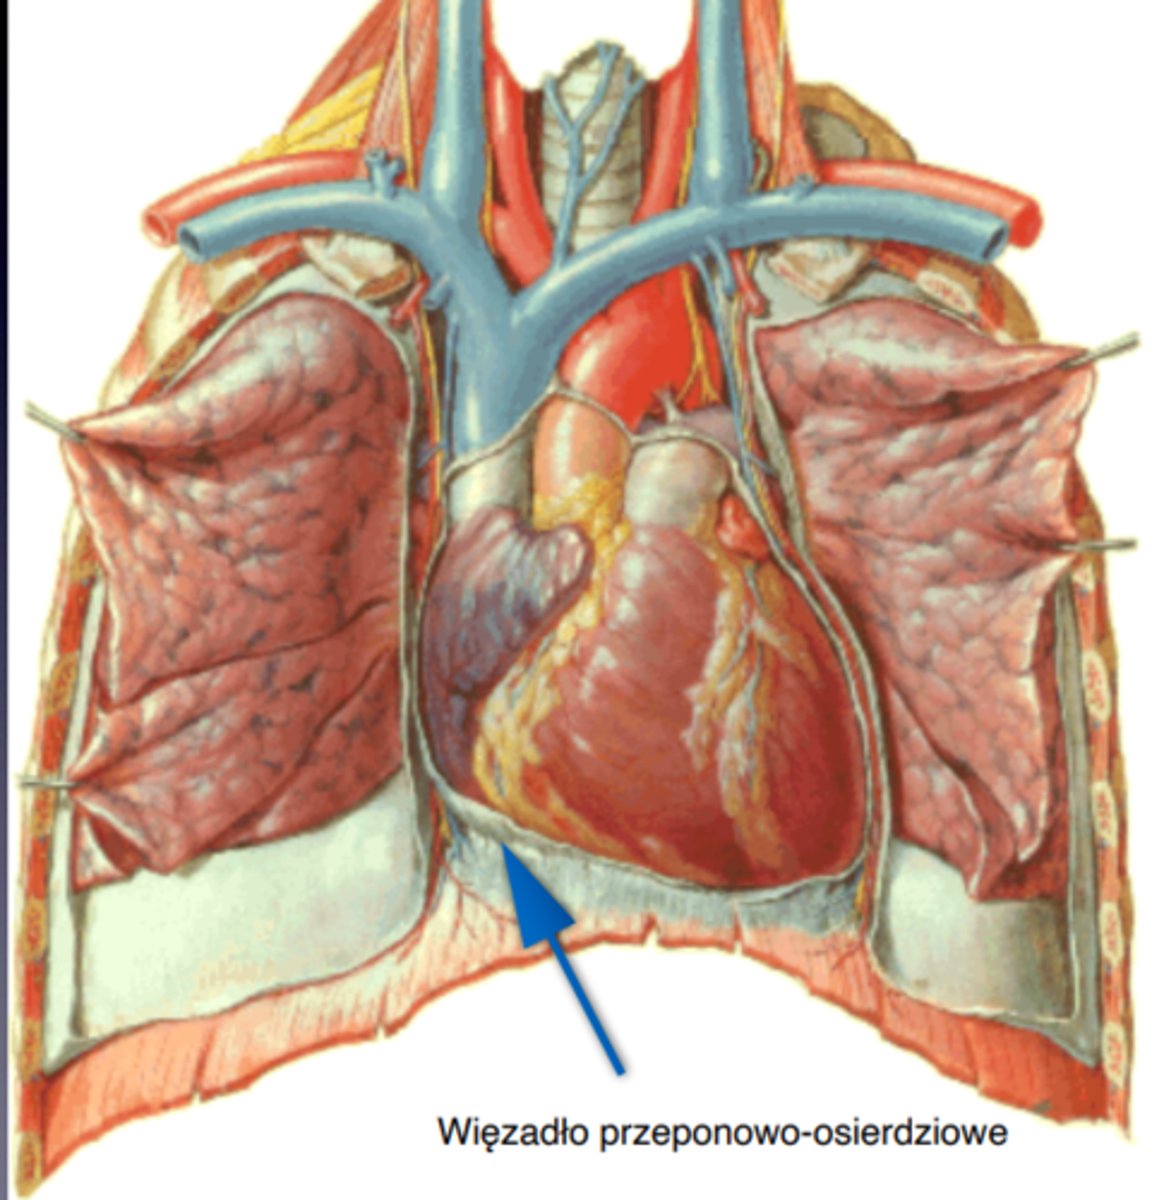

od dołu łączy się z przeponą i tworzy więzadło przeponowo-osierdziowe

więzadło przeponowo-osierdziowe

phrenicopericardial lig.